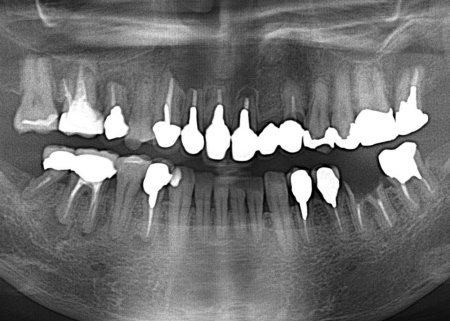

拝見したところ、欠損した左上前歯(側切歯)を補うために、両隣の歯を土台として人工歯を連結したブリッジが装着されていました。

しかし、レントゲン撮影をして詳しく検査を行うと、ブリッジの土台になっている2本の前歯(中切歯、犬歯)に虫歯が生じており、それにより歯がぐらぐらしていることが判明しました。

仮に虫歯を治療したとしても、残っている歯の部分が少ないため、再びブリッジを装着することは困難です。

また、このまま放置すると虫歯が進行し、周囲の歯や骨に細菌感染が広がるリスクもあるため、早急に治療をする必要があると診断しました。

インプラントをしっかりと支えるためには十分な骨の高さや厚みが必要ですが、前歯は唇側の骨が薄く、抜歯後に骨が吸収されて骨量が失われやすい部位です。

そこで今回は、抜歯と同時にインプラントを埋め込む抜歯即時埋入と、ご自身の歯質(歯を構成する成分)を唇側に残すソケットシールドテクニックを併用する治療を計画しました。

これは健全な歯質が存在する場合に限った治療方法ですが、左上前歯2本の歯質を意図的に少し残すことで、抜歯後に起こる骨や歯茎の吸収をできる限り抑え、自然なかたちでの骨量の維持が期待できます。